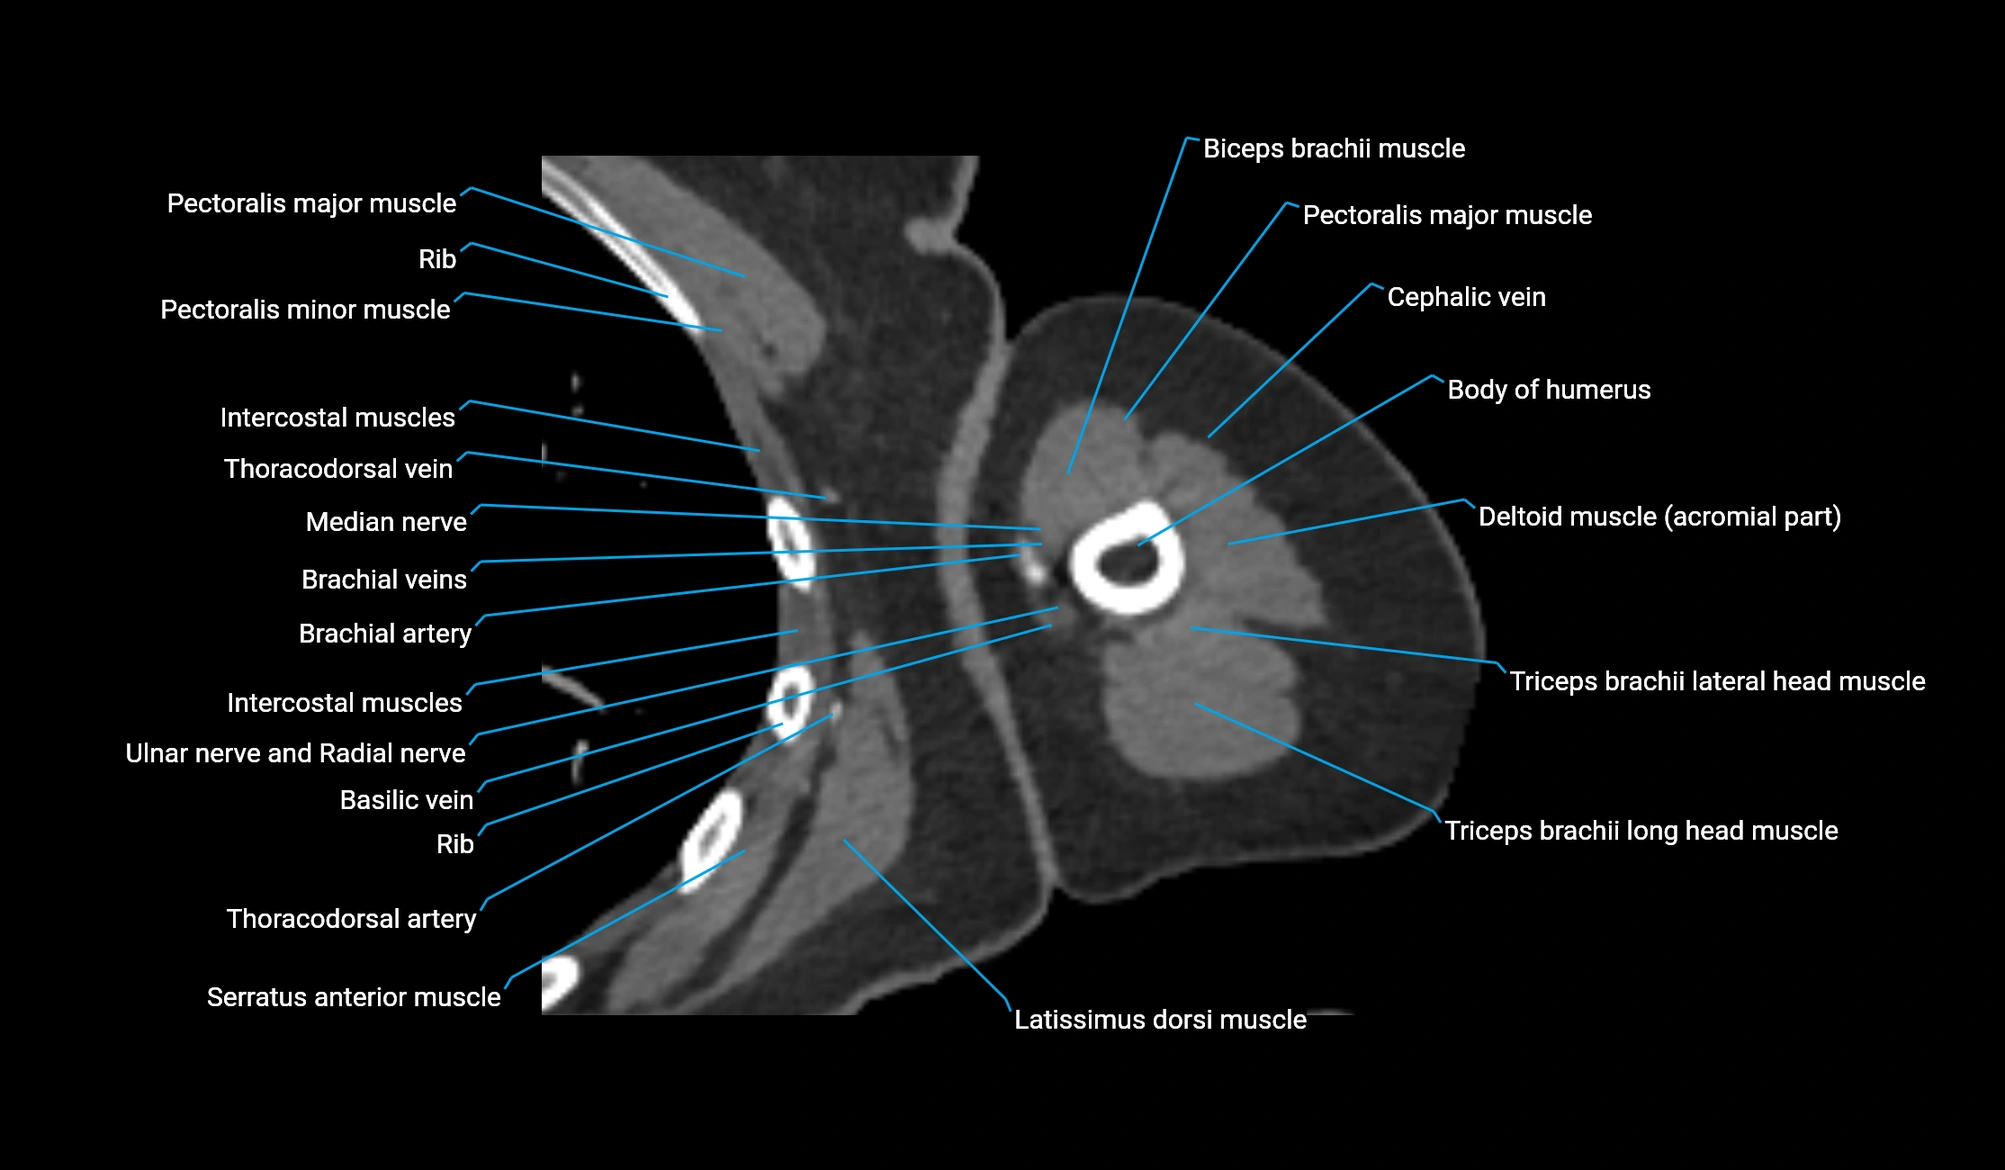

- Body of humerus

- Brachialis muscle

- Cephalic vein

- Deltoid muscle

- Lateral head of triceps brachii muscle

- Long head of triceps brachii muscle

- Median nerve

- Pectoralis major muscle

- Pectoralis minor muscle

- Thoracodorsal artery

- Triceps brachii muscle